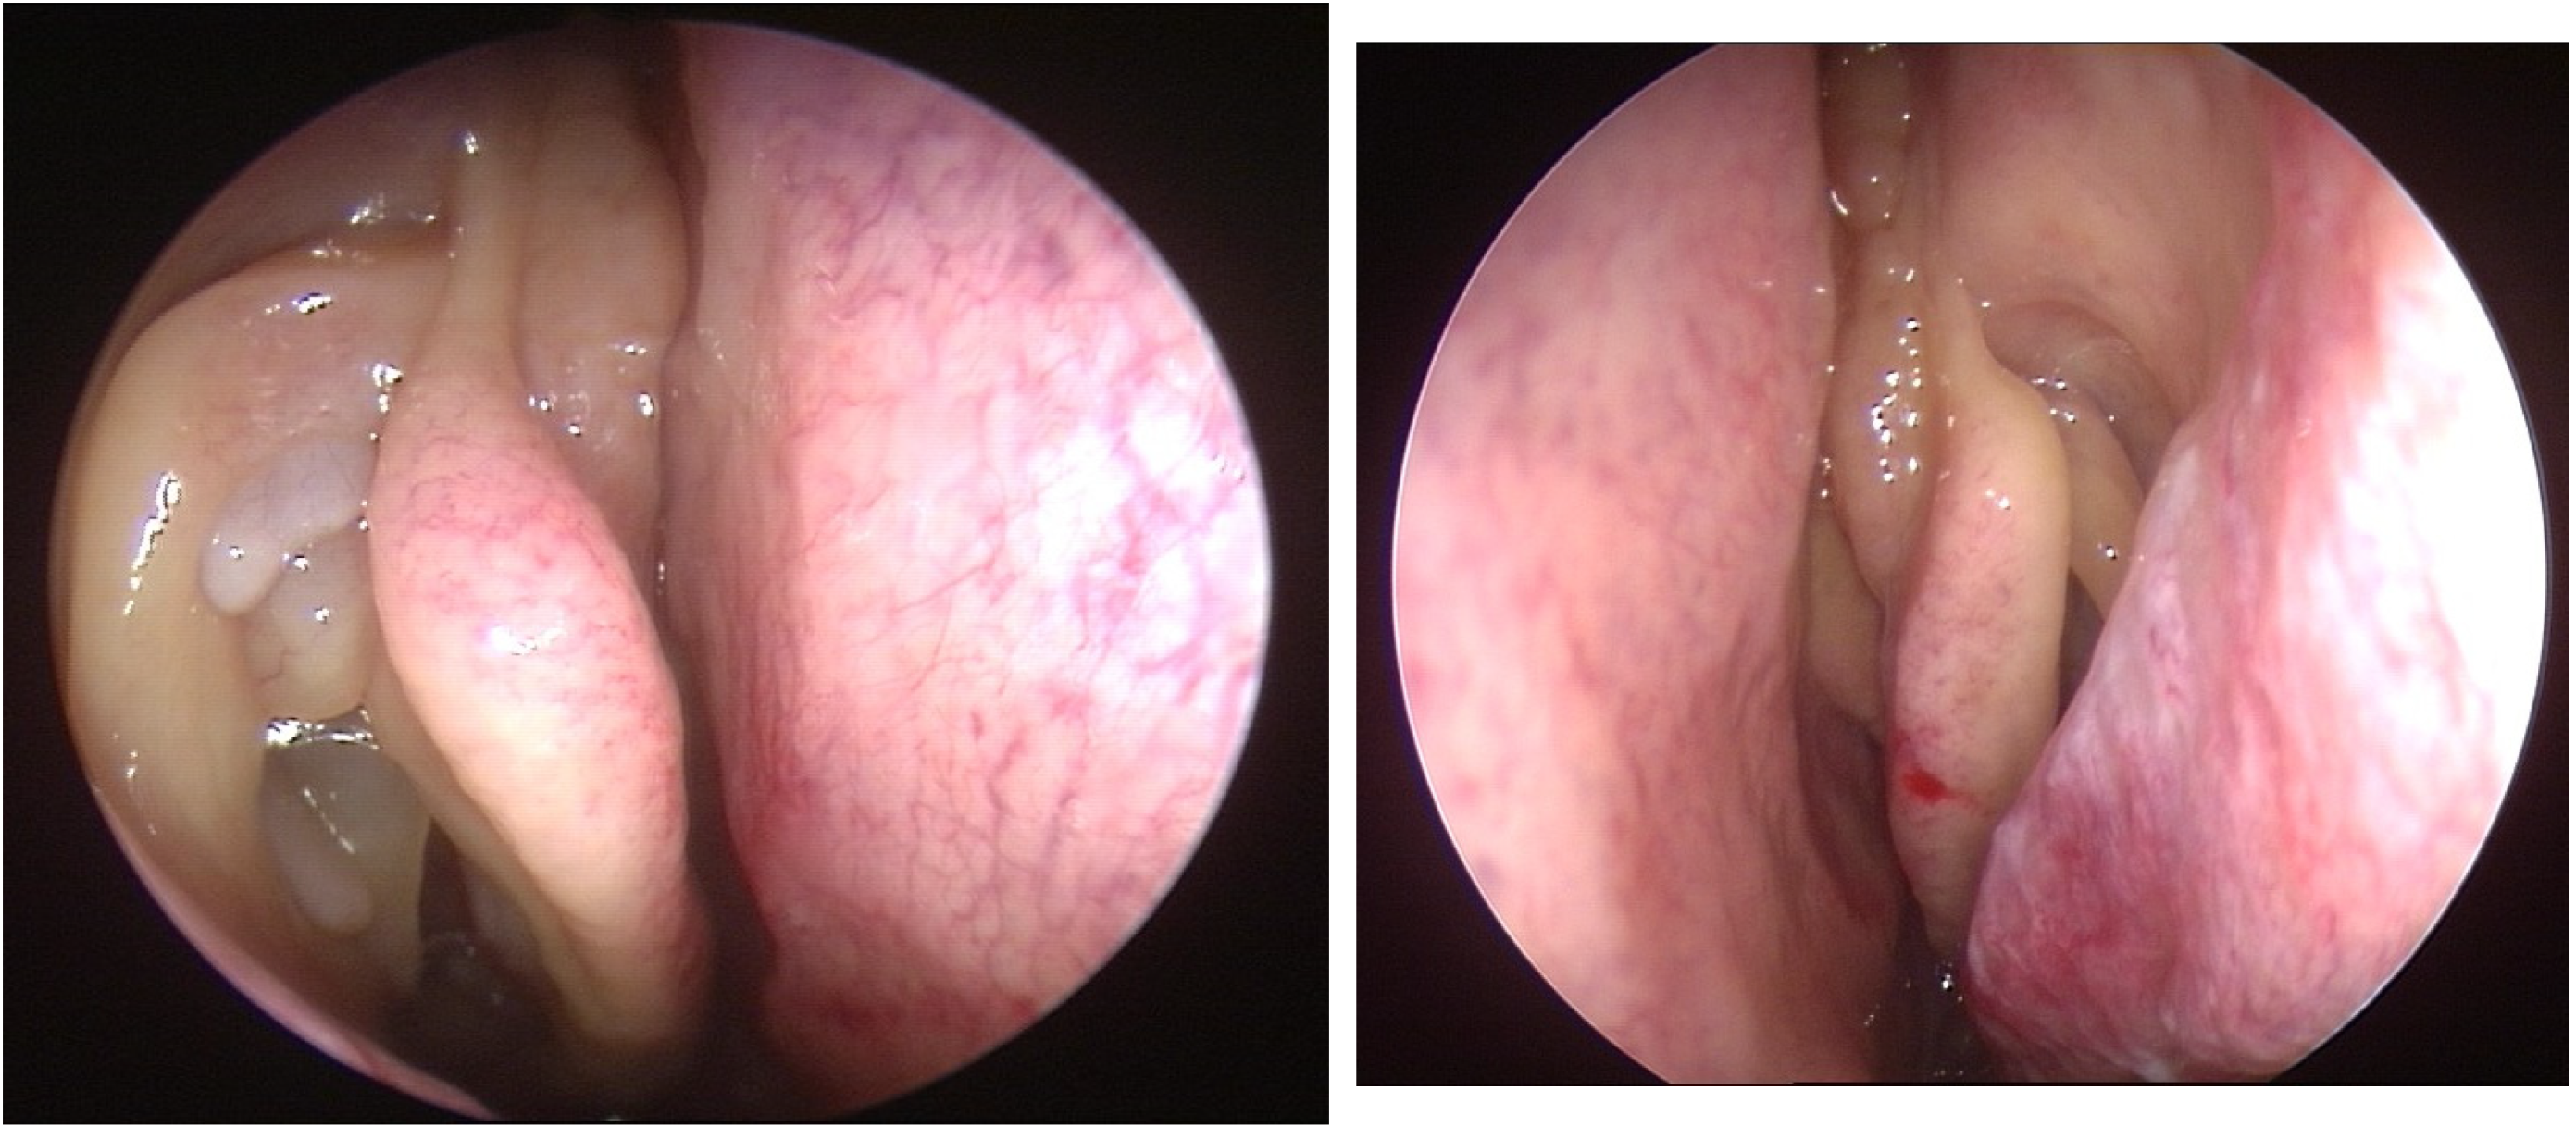

- 0 = no polyps;

- 1 = polyps confined to the middle meatus;

- 2 = multiple polyps occupying the middle meatus;

- 3 = polyps extending beyond the middle meatus;

- 4 = polyps completely obstructing the nasal cavity.

- 1 = small polyps in the middle meatus not reaching the inferior border of the middle meatus;

- 2 = nasal polyps reaching below the lower border of the middle meatus;

- 3 = large polyps reaching the lower border of the inferior turbinate or polyps medial to the middle turbinate;

- 4 = large nasal polyps causing complete obstruction of the inferior nasal cavity.

- Djupesland, P.; Reitsma, S.; Hopkins, C.; Sedaghat, A.; Peters, A.; Fokkens, W.J. Endoscopic grading systems for nasal polyps: Are we comparing apples to oranges? Rhinology 2022, 60, 169–176. [Google Scholar] [CrossRef] [PubMed]

- Gevaert, P.; Gevaert, P.; De Craemer, J.; De Craemer, J.; Bachert, C.; Bachert, C.; Blauwblomme, M.; Blauwblomme, M.; Chaker, A.; Chaker, A.; et al. European Academy of Allergy and Clinical Immunology position paper on endoscopic scoring of nasal polyposis. Allergy 2023, 78, 912–922. [Google Scholar] [CrossRef] [PubMed]